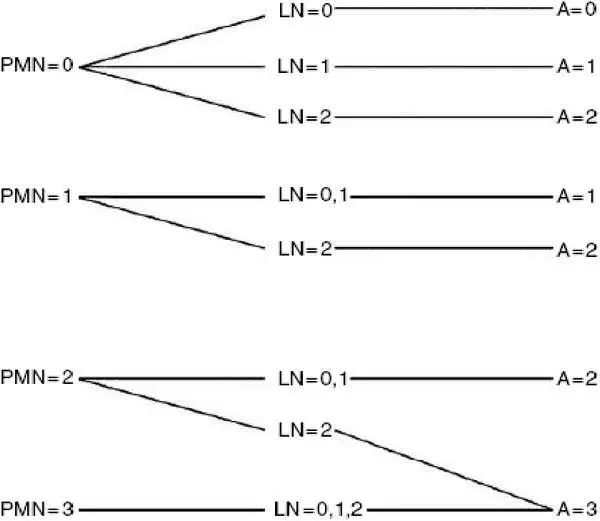

■ А – степень активности воспаления в печени.

• А=0 – минимальная активность,

• А=1 – умеренная активность,

• А=2 – выраженная активность воспаления в печени.

Рисунок 4 – Алгоритм для оценки воспалительной активности по шкале METAVIR.